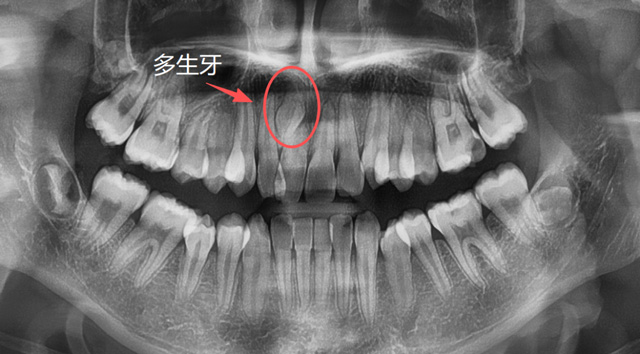

儿童上颌多生牙

建议家长在小朋友处于替牙期的时候,不管有没有牙疼,都找专业的口腔医生进行检查,必要时拍片看一下牙胚的数量有无出入,关注一下牙齿是否按正常的顺序完成了替换,如有异常情况,可以及时干预。

牙根的形态、数量是天生的,无法后天干预,但是对于部分异位牙、埋伏牙,我们可以在小朋友替牙期的这个阶段通过相应的医学手段来干预,避免一些成年后的拔牙。

长在上颌窦、鼻腔方向的异位牙,长在牙槽骨深处的多生牙,常常埋伏于骨内,需要骨开窗才能拔除,具有一定的难度。

那么,以上这些异常情况的牙都是天生的吗?能不能预防呢?